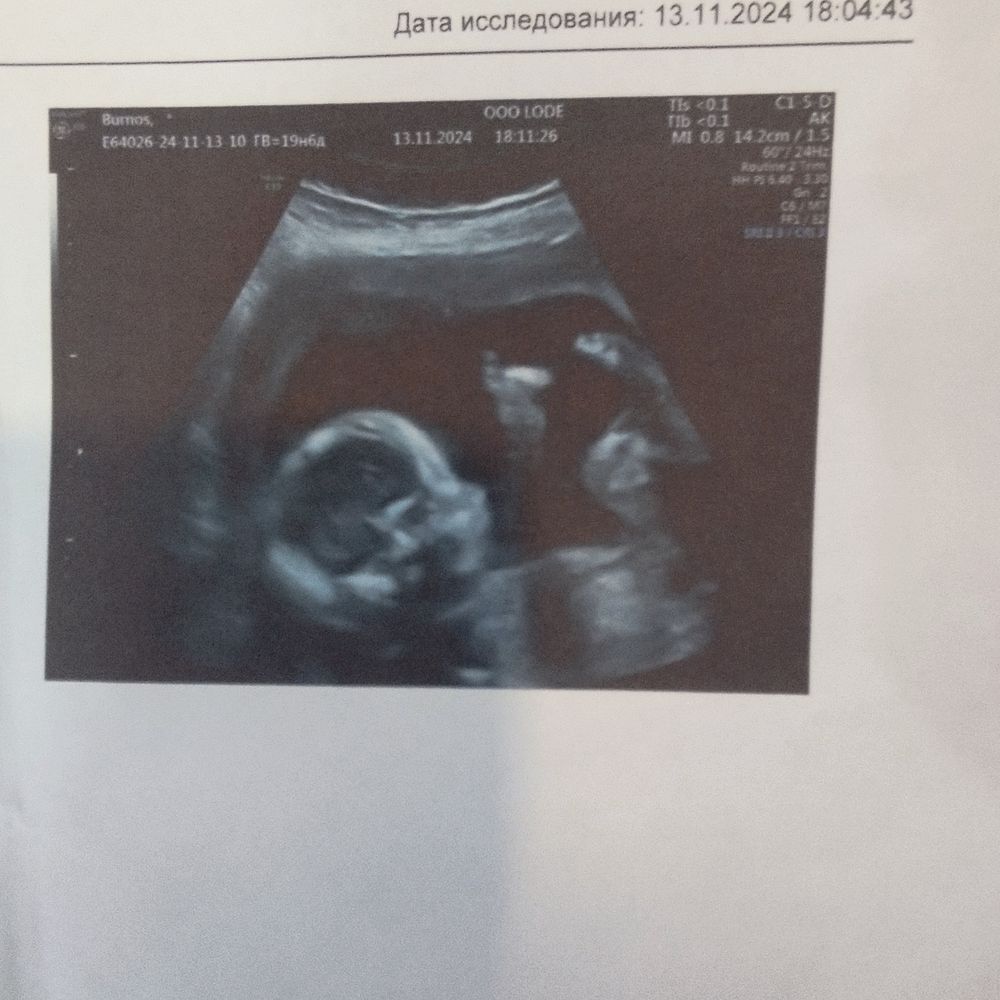

Привет половина беременности

Девочка😀

Пол на первом скрининге Определение Пола по половому бугорку